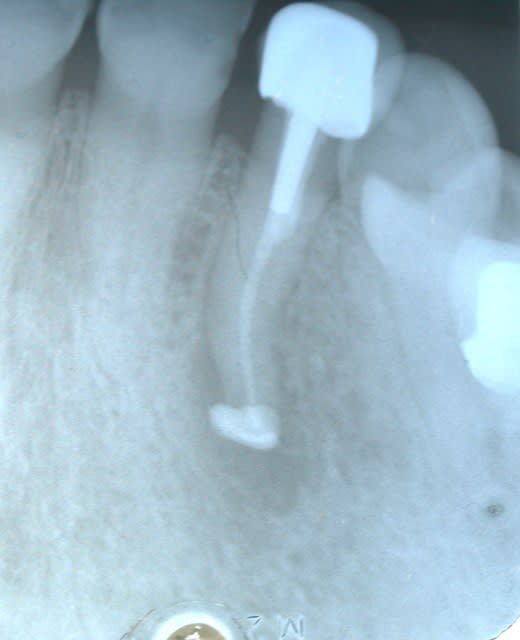

ah la voila.

un cas de necrose pas du tout asymptomatique .

bosse en vestibulaire .

douleur a la pression.

là on ne peut pas parler de bouchons a l apex ou quoi que ce soit

hygiene tres moyenne

protheses en bois

et on remarquera que la gencive marginale n es pas top

endo impossible a faire

et donc pas de rescection puisque pas d'endo.

l outil extraction reimplantation s impose alors.